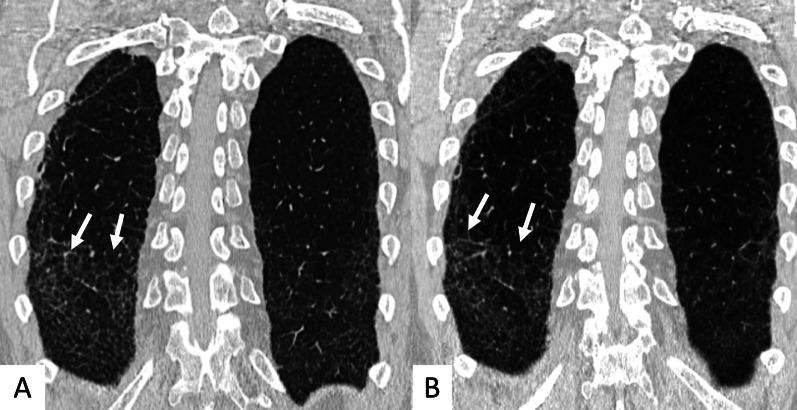

Connective tissue diseases (CTDs) include a spectrum of disorders that affect the connective tissue of the human body; they include autoimmune disorders characterized by immune-mediated chronic inflammation and the development of fibrosis. Lung involvement can be misdiagnosed, since pulmonary alterations preceded osteo-articular manifestations only in 20% of cases and they have no clear clinical findings in the early phases. All pulmonary structures may be interested: pulmonary interstitium, airways, pleura and respiratory muscles. Among these autoimmune disorders, rheumatoid arthritis (RA) is characterized by usual interstitial pneumonia (UIP), pulmonary nodules and airway disease with air-trapping, whereas non-specific interstitial pneumonia (NSIP), pulmonary hypertension and esophageal dilatation are frequently revealed in systemic sclerosis (SSc). NSIP and organizing pneumonia (OP) may be found in patients having polymyositis (PM) and dermatomyositis (DM); in some cases, perilobular consolidations and reverse halo-sign areas may be observed. Systemic lupus erythematosus (SLE) is characterized by serositis, acute lupus pneumonitis and alveolar hemorrhage. In the Sjögren syndrome (SS), the most frequent pattern encountered on HRCT images is represented by NSIP; UIP and lymphocytic interstitial pneumonia (LIP) are reported with a lower frequency. Finally, fibrotic NSIP may be the interstitial disease observed in patients having mixed connective tissue diseases (MCTD). This pictorial review therefore aims to provide clinical features and imaging findings associated with autoimmune CTDs, in order to help radiologists, pneumologists and rheumatologists in their diagnoses and management.

结缔组织病(CTDs)包括一系列影响人体结缔组织的疾病;它们包括以免疫介导的慢性炎症和纤维化发展为特征的自身免疫性疾病。肺部受累可能会被误诊,因为肺部改变仅在20%的病例中先于骨关节炎表现出现,且在早期阶段没有明确的临床发现。所有肺部结构都可能受累:肺间质、气道、胸膜和呼吸肌。在这些自身免疫性疾病中,类风湿关节炎(RA)的特征是普通型间质性肺炎(UIP)、肺结节和伴有空气潴留的气道疾病,而系统性硬化症(SSc)常表现为非特异性间质性肺炎(NSIP)、肺动脉高压和食管扩张。NSIP和机化性肺炎(OP)可见于多发性肌炎(PM)和皮肌炎(DM)患者;在某些情况下,可观察到小叶周围实变和反晕征区域。系统性红斑狼疮(SLE)的特征是浆膜炎、急性狼疮性肺炎和肺泡出血。在干燥综合征(SS)中,HRCT图像上最常见的表现是NSIP;UIP和淋巴细胞间质性肺炎(LIP)的报道频率较低。最后,纤维化NSIP可能是混合性结缔组织病(MCTD)患者中观察到的间质性疾病。因此,本图像综述旨在提供与自身免疫性CTDs相关的临床特征和影像学表现,以帮助放射科医生、呼吸科医生和风湿病科医生进行诊断和管理。